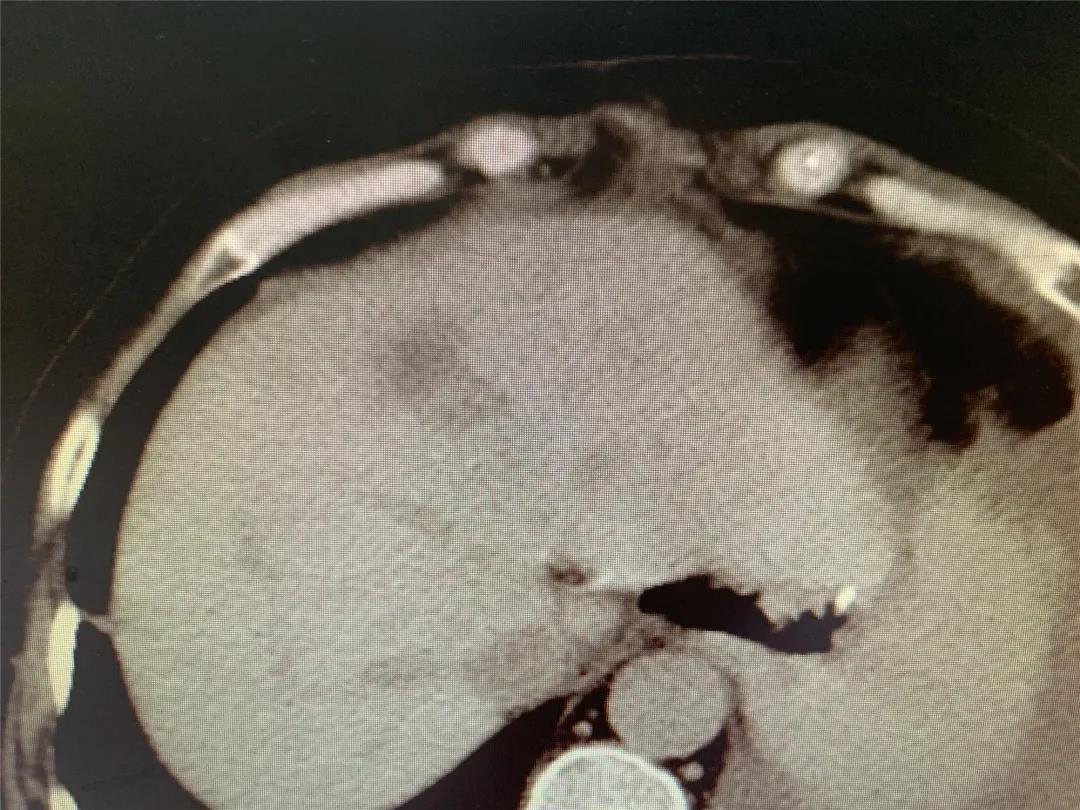

术后1个月复查上腹部CT

8月前患者就诊于晋城市某医院行胃镜示:胃癌,病理示:腺癌。进一步行腹部增强CT示:贲门胃底小弯侧占位,周围见肿大淋巴结;肝内低密度肿块影,考虑转移。遂就诊于和济医院,入院诊断为:“1.胃癌肝转移(cT4N2M1) 2.肝脏多发囊肿3.原发性高血压(2级,低危组)4.卵巢囊肿切除术后”。经医院消化病中心MDT讨论,并与患者及家属充分沟通后,决定先为其行转化治疗(方案:DOS)。转化治疗2个周期后患者症状明显好转,体重增加约10kg。肿瘤原发病灶较前缩小、肝脏转移灶较前缩小。继续行转化治疗(方案:DOS)3个周期后,患者肿瘤原发病灶较前增大、肝脏转移灶较前继续缩小。经和济医院消化病中心再次MDT讨论并与患者及家属充分沟通后,决定手术治疗。术中胃肠外科张晋杰医师、张康康医师先行腹腔镜辅助根治性全胃切除术+D2淋巴结清扫+Roux-en-Y吻合术,术中邀请肝胆外科主任程丹桂主任医师、刘军廷副主任医师以及超声室武鹏副主任医师行彩超定位下左肝转移病灶射频消融术。术中射频消融在保证对左肝转移病灶精准处理的前提下,对肝脏以最小的创伤,起到最佳的治疗效果,整个手术创伤小,术后第3日开始进流食,5日行上消化道造影提示:未见吻合口瘘。目前患者已恢复正常进食,痊愈出院。